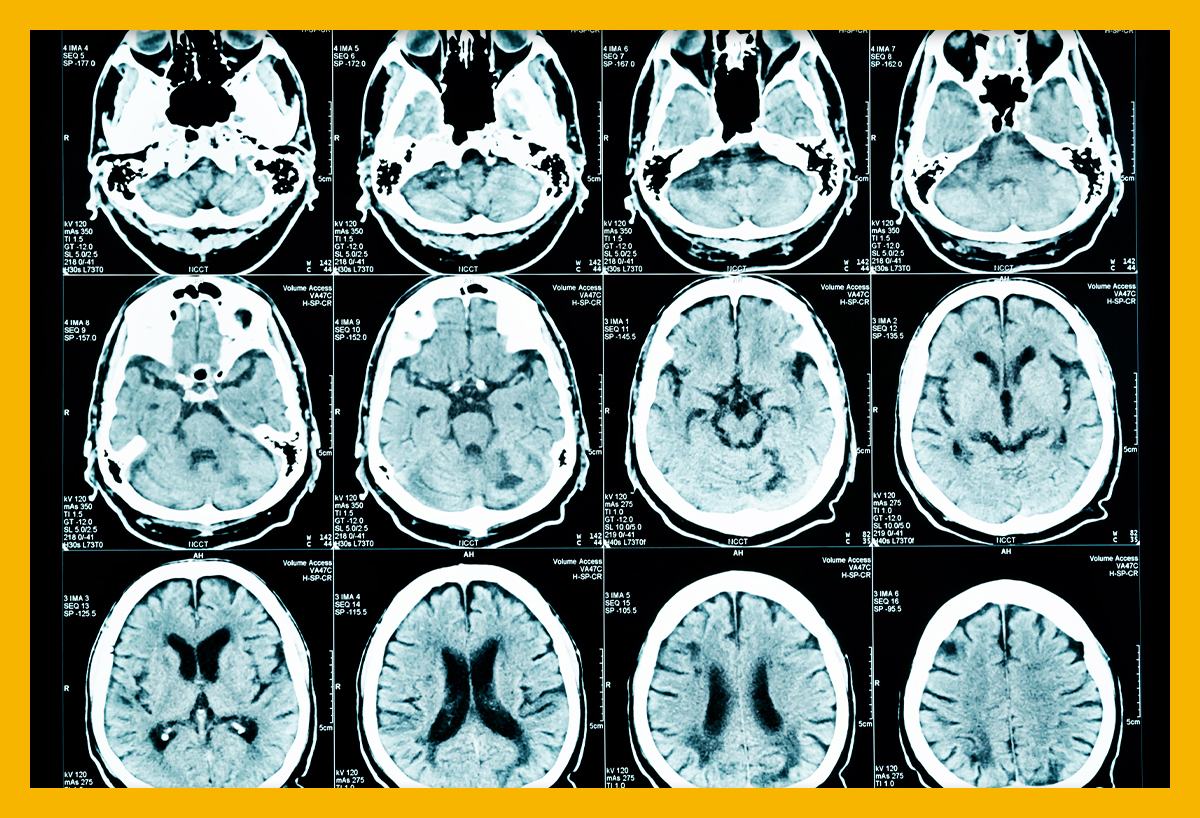

뇌경색이란 무엇인가요?

뇌경색은 혈관이 좁아지거나 막히면서 발생하는 뇌의 손상입니다. 이는 주로 혈전이나 색전으로 인해 발생하며, 그로 인해 뇌의 특정 부분에 oxygen과 영양소가 공급되지 않게 됩니다. 이 상태가 지속되면 뇌세포는 영구적으로 손상을 입거나 죽게 됩니다.

뇌경색에는 두 가지 주요 유형이 있습니다. 첫 번째는 허혈성 뇌경색으로, 대개 혈전이 혈관을 막아 발생합니다. 두 번째는 출혈성 뇌경색으로, 뇌혈관이 파열되거나 약해져 출혈이 발생하는 것입니다. 본 포스팅에서는 주로 허혈성 뇌경색의 초기 증상에 대해 설명드리겠습니다.